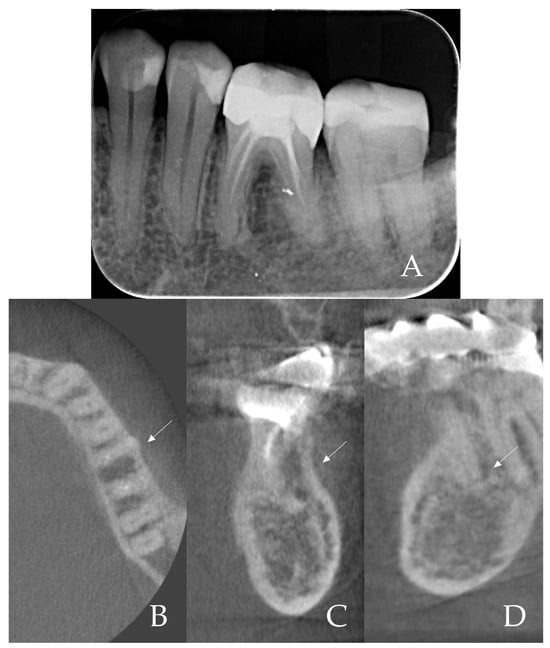

- Root sectioning: After performing mandibular nerve block anesthesia, the crown of tooth #36 (Figure 2A) was removed (decoronation was performed) (Figure 2B). The mesial and distal roots were then separated buccolingually using a long-shanked, straight diamond bur in a high-speed handpiece with copious irrigation (Figure 2C). The preoperative CBCT was consulted to guide the depth and orientation of the cuts, accounting for the roots’ length, curvature, and angulation.